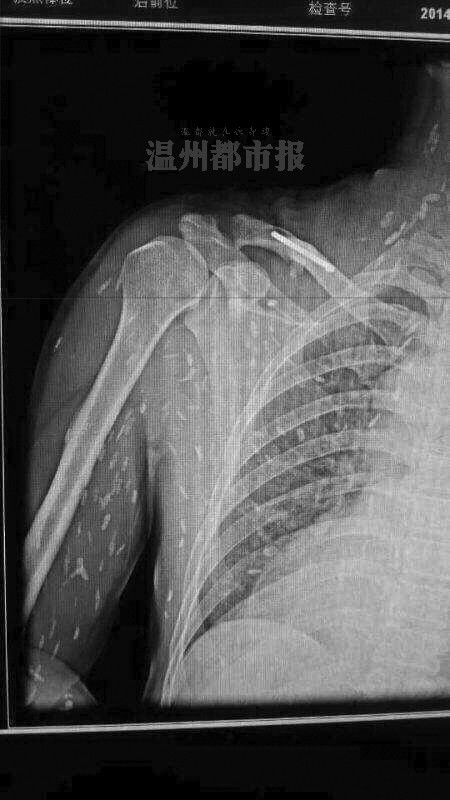

网络流传的满是寄生虫的X光片照片。图片来自网络

这两天,一张布满白点、看起来像长满寄生虫的图在网上热传。配图文字称:“瑞安一病人爱吃生鱼片,满身寄生虫?”

由于朋友圈内容语焉不详,且存在知识性错误,如将X光片说成CT片,加上与好友对话不完整,截屏被发网上后,网友纷纷误以为病例来自瑞安,并对CT片上能显示寄生虫表示极大怀疑。

专家分析:可能是虫体钙化留下的斑点

一位名为“doctor吴”的网友,在一论坛上发表了一篇《对微信流行的寄生虫一事个人见解》。文中,“doctor吴”表示,他从医学角度上对该片持怀疑态度。他认为,寄生虫的密度跟人体密度相仿,简单普通的X光并不能让它显影,CT下基本不能看到,除非聚集成团或者蛔虫。因为在胆道中,胆汁密度比虫体低,虫体密度与胆管相若,CT显影为胆道堵塞。

与此同时,他还提到,如果虫体死亡后钙化,那是可以在X光片中显影的。

这一说法得到我市寄生虫学专家认可。温州医科大学基础医学院副教授、寄生虫学教研室副主任黄慧聪认为,看到这样一张X光片,假如片子本身是真实的,通常会认为是寄生虫的软组织虫体广泛分布的皮下肌肉的钙化病灶。“通俗点说,就是寄生虫在体内死亡后钙化留下的斑点。”

黄慧聪指出,活的寄生虫是游走不定的,很难被X光片拍到,在直接影像学上是看不出来的。一般是形成虫囊或钙化后才容易被X光片观察到。但形成虫囊或钙化需要较长时间,通常要半年以上。如果像网上传的那样,由于食用生食短时间内出现这样的钙化灶,这种说法是值得怀疑的。

此外,他还说,出现图片所示那样广泛分布的钙化灶,通常考虑是旋毛虫病。这可能是生吃肉类导致,通过吃鱼感染的极为罕见。假如不是旋毛虫病,也可能是肺吸虫病。后者一般是通过生食溪蟹、蝲蛄(俗称小龙虾)等感染的,患病后虫体可能会游走,像图片里显示的这么密集,他还是第一次看到。

多位医学专业人士指出,单从这张X光片上看,图中白点如果真是寄生虫钙化后的显影,很像是囊尾蚴,这是扁形动物门绦虫纲幼虫的一种类型。

由于图片原始出处很难查找,这张令人毛骨悚然的X光片真伪难辨。相关人士分析指出,一者不能排除这张照片经过PS修改伪造的可能性,二者即使照片是真的,图中的白色斑点也有可能是患者体外衣物上或躯体表面的附着物。